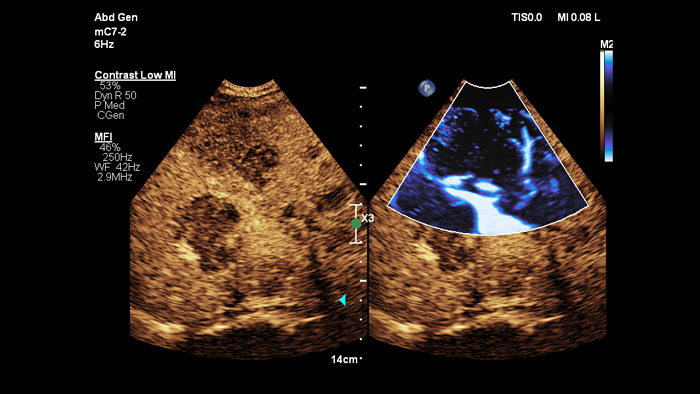

Ultraschall-Kontrastmittel können die Rolle des Ultraschalls verändern: Verstärkungsmuster von Leberläsionen können von Klinikteams in Echtzeit untersucht werden. Bei Ultraschallgeräten von Philips sind kontrastmittelverstärkte Ultraschalluntersuchungen nahtlos in den Standardablauf integriert.

Jeder Mensch ist anders. Die PureWave Kristalltechnologie bietet ein verbessertes Eindringvermögen bei schwer schallbaren Patienten ohne Abstriche bei der Detailauflösung, der Doppler-Empfindlichkeit und dem kontrastmittelverstärkten Ultraschall (CEUS).

Die PureWave Kristalltechnologie ist der grösste Durchbruch bei piezoelektrischem Schallkopfmaterial seit 40 Jahren und ist 85% effizienter als herkömmliche piezoelektrisches Schallkopfmaterial, was zu herausragenden Ergebnissen bei unterschiedlichsten Patienten führt.